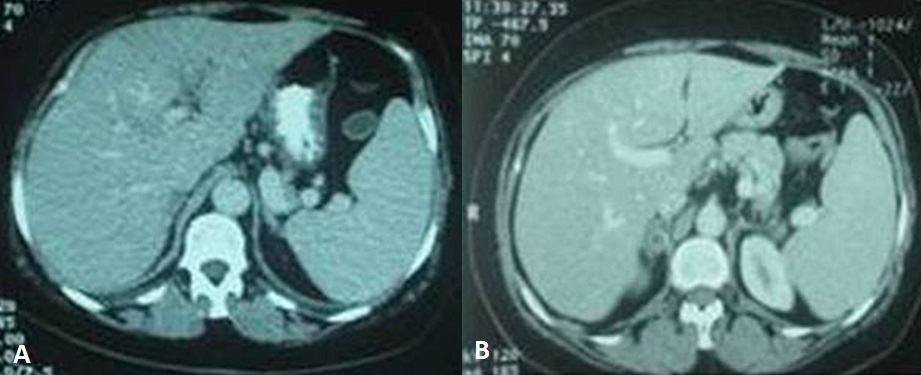

La fréquence des thromboses veineuses profondes au cours du syndrome de Cushing varie de 7 à 25%. Elles sont secondaires à des mécanismes multiples : élévation des taux des facteurs VIII, IX et de Von Willebrand, une réduction du TCA et une augmentation du TP. Nous rapportons l'observation d'une thrombose de la veine porte dont l'exploration étiologique a conduit au diagnostic du syndrome de Cushing. Il s'agissait d'une patiente âgée de 66 ans, sans antécédents pathologiques, hospitalisée pour une douleur intense et brutale de l'hypocondre droit. L'examen trouvait une obésité facio-tronculaire, une tension artérielle à 150/90 mmHg, des vergetures larges et pourpres au niveau du ventre et une sensibilité de l'hypochondre droit. Le scanner abdominal objectivait une thrombose de la branche portale gauche et un adénome surrénalien droit de 2 cm de grand axe, de densité spontanée estimée à 0,4 UH et un Wash out supérieur à 50%. Le bilan hormonal montrait un taux normal d'acide vanylmandélique urinaire, une élévation du cortisol libre urinaire à 233 µg/24h avec une cortisolémie sous freinage minute à 76 ng/ml. Le bilan étiologique de la thrombose de la veine porte était négatif (hémogramme normal, absence de lésion tumorale hépatique et de foyer infectieux intra-abdominal, taux normaux de protéine C, d'anti-thrombine, de protéine S et de résistance à la protéine C activée, anticorps antiphospholipides négatifs). La patiente était mise sous anticoagulant et confiée à la chirurgie. La recherche des signes cliniques et biologiques du syndrome de Cushing doit figurer dans le bilan étiologique d'une thrombose veineuse portale sans cause évidente.